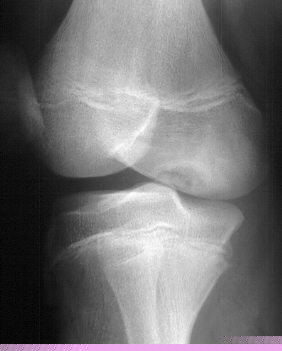

with a mildly positive apprehension test. Based on the radiographs

and his clinical exam an arthroscopic examination was performed.

At arthroscopy the medial femoral condylar defect was not apparent,

but a large retinacular tear was discovered. Also, the patient

had an osteochondral fracture of the lateral femoral condyle and

a free 7 mm by 5 mm intraarticular cartilage fragment.

Patella

alta and Excessive Q angle are two risk factors for this type

of patellar dislocation.